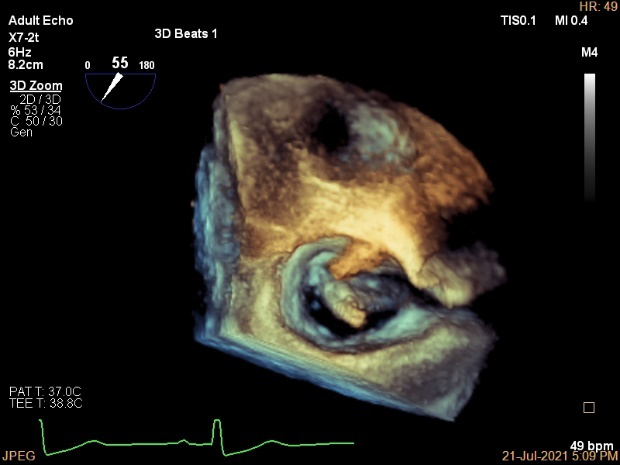

术前超声诊断:

长轴:左室下后壁节异,LAV:101ml,LVEDV:239ml

Bicom:MR(重度),返流束宽15.8mm,返流面积10.6cm²

PISA法定量EROA:0.69cm²,Rvol:168ml,RF:55%

肺静脉血流频谱呈收缩期反向

3D MV View

3D-color MV view:血流主要来源于2区近3区

Qlab软件勾画估测瓣口面积约:6.16cm²

二尖瓣口平均跨瓣压差:1mmHg

TEE Bicom返流量评估

TEE 4-Ch view返流量评估

术中超声引导:

确定房间隔穿刺点:靠后

穿刺点高度测量:4.14cm

2D视图下测量大鞘长度2.2cm

2D视图下建立trajectory

3D视图打开夹子

3D视图下调Rotate,定位2区

X-plane:下夹子尝试捕获2区

夹子逐渐夹闭后,2区返流逐渐减少

3D:测量前叶长21.2mm,后叶长10.2mm

X-plane:计算前叶捕获长度6.8mm,后叶捕获长度6.5mm

夹子放置后二尖瓣口平均跨瓣压差:3mmHg

肺静脉血流频谱恢复正常

3D视图下观察二尖瓣双孔形态

3D-color:残余少量返流